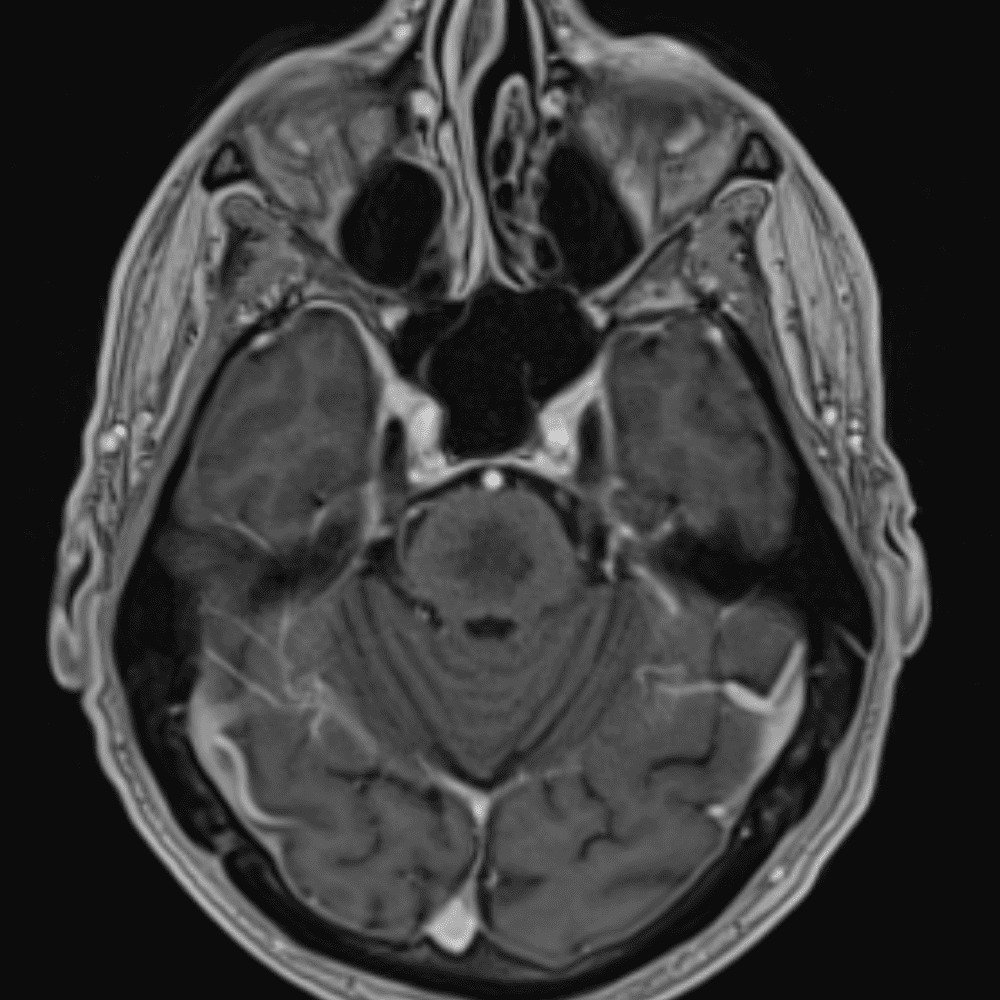

๋ฏธ๋ฌ˜ํ•˜๊ฑฐ๋‚˜ ์–ด๋ ค์šด ์‚ฌ๋ก€์™€ ์ผ๋ถ€ ์ •์ƒ ์‚ฌ๋ก€๋ฅผ ํฌํ•จํ•˜์—ฌ ๋‹น์ง์„ ์‹œ๋ฎฌ๋ ˆ์ด์…˜ํ•ฉ๋‹ˆ๋‹ค.

50 ์‚ฌ๋ก€